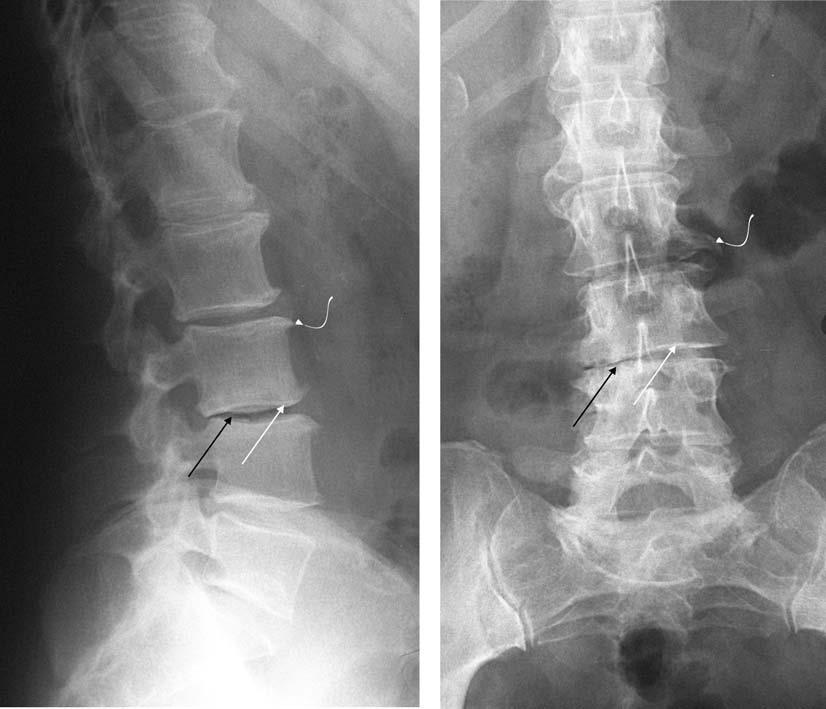

Рентген поясницы: анатомические особенности и медицинские исследования

Раздел: Фотоэссе